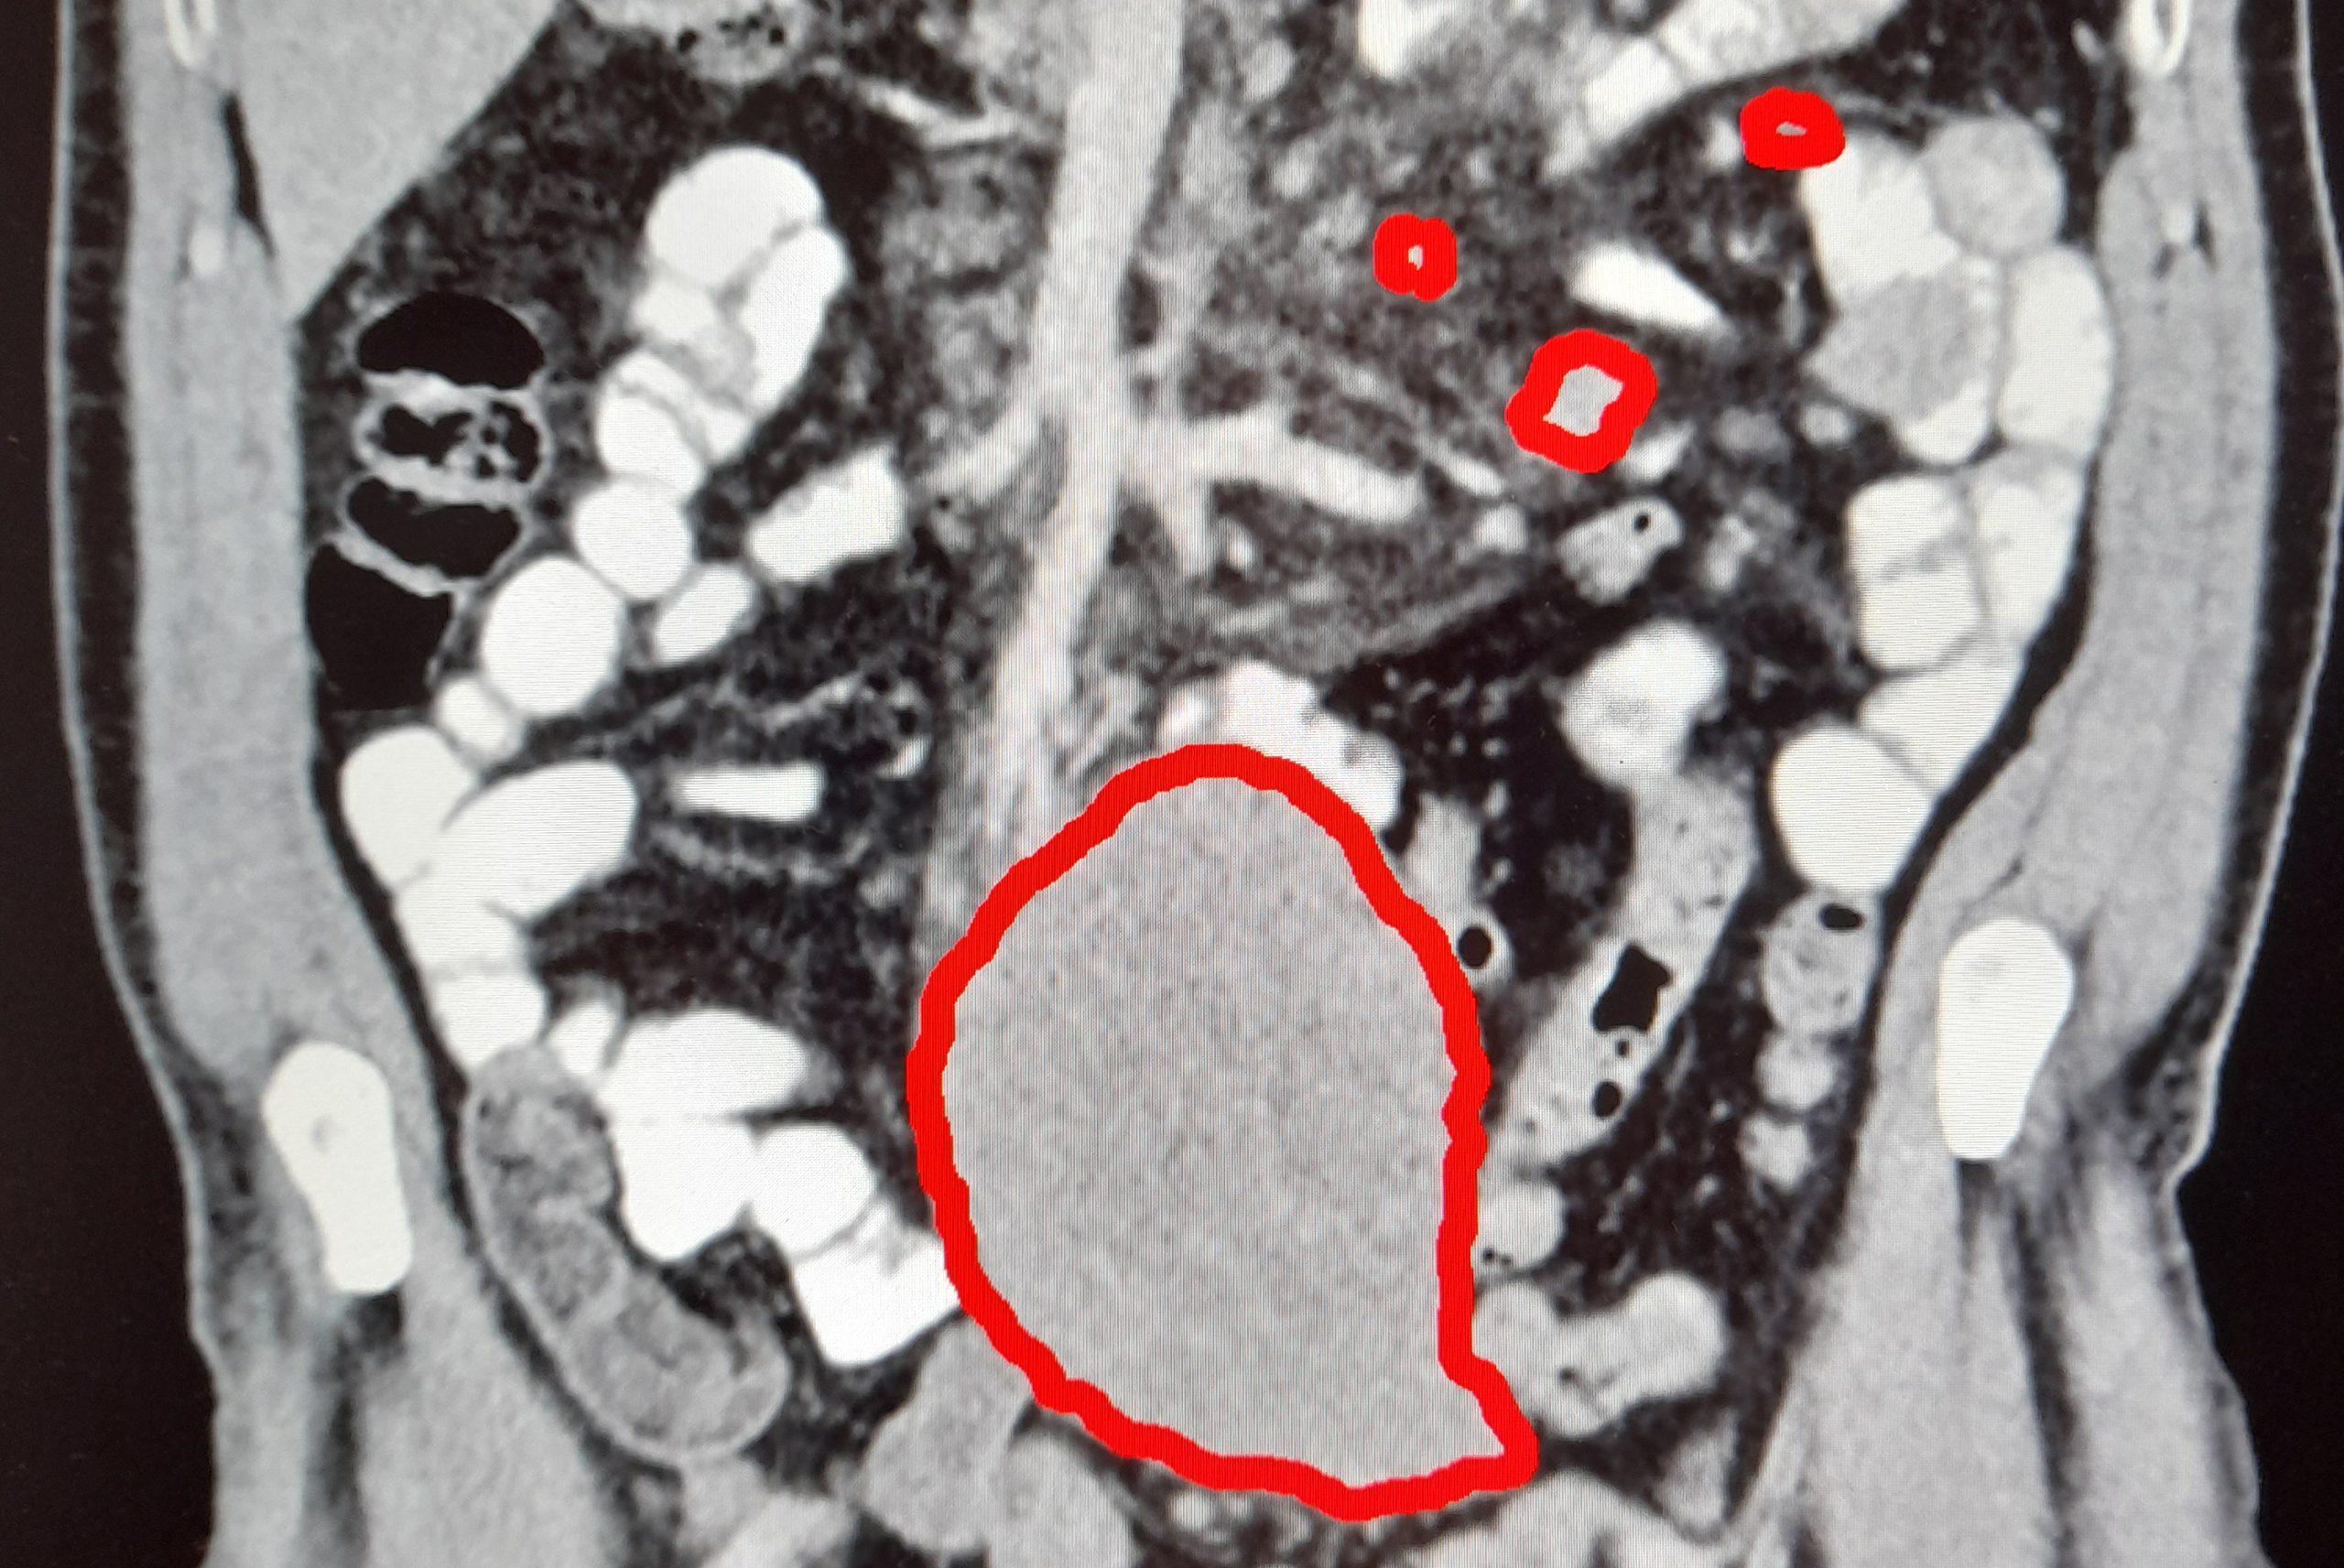

Diagnose Krebs

Dann ein Zufallsbefund: Da ist etwas, was nicht dahin gehört!

Sie haben Krebs. Einige Zellen halten sich nicht an die übliche Zellteilung und motieren nach einem eingenen Plan.